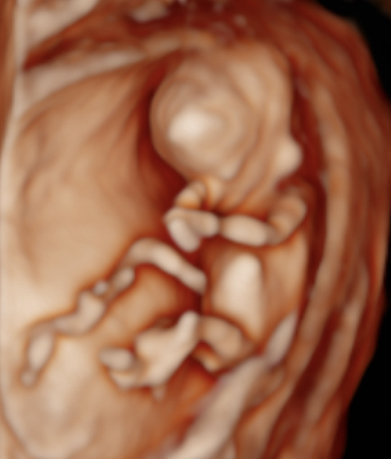

Genetický ultrazvuk Fetální echokardiografie Dopplerovské vyšetření krevního oběhu miminka a placenty Screening předčasného porodu Screening preeklampsie a zaostávání růstu miminka Vyšetření vícečetných těhotenství 3D-4D ultrazvuk Určení pohlaví miminka

Používáme špičkové přístroje a všichni naši lékaři jsou držiteli certifikátu Fetal Medicine Foundation (FMF) na všechny typy ultrazvukových vyšetření v těhotenství. Při vyšetření miminka se vždy řídíme FMF protokoly, prohlížíme i drobné detaily a ke zpřesnění používáme kombinaci 2D a 3D ultrazvuku. V průběhu vyšetření vám vždy vysvětlujeme, co právě vyšetřujeme a co s námi můžete vidět na monitoru. Po skončení vyšetření vám srozumitelně vysvětlíme výsledky (a případně závažnost situace) a navrhneme další postup.